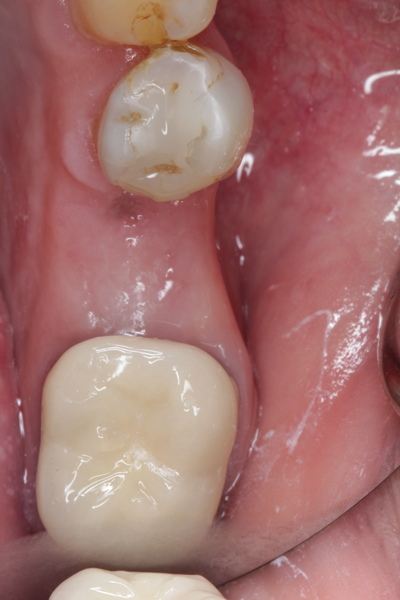

Fig 9. At 8 weeks postoperative, the ridge was keratinized.

Figure 9

Fig 10. At 3 months postoperative, the flap was elevated, demonstrating a restored buccal plate of bone.

Figure 10

Fig 11. An implant was placed in regenerated bone.

Figure 11